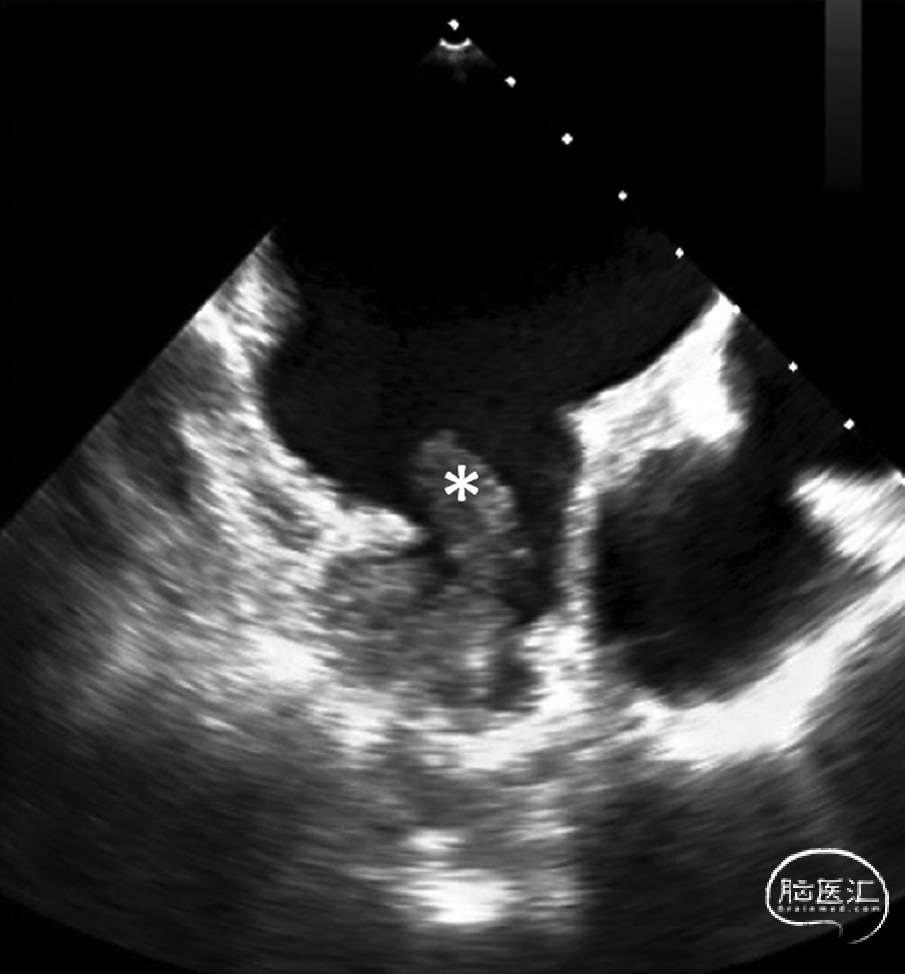

多项研究报告称,左心房内形成的大多数血栓起源于左心耳:例如,在接受心脏手术的房颤患者样本中,75%的左心房血栓来源于此;²³ 在近期发生卒中的房颤患者样本中,这一比例为82%;²⁴ 而在无卒中的非瓣膜性房颤患者中,比例高达91%。²⁵ 无论是经食管超声心动图(图1)还是心脏计算机断层扫描(图2),对于检测左心耳血栓都具有高度的敏感性和特异性。²⁶ 在合并房颤的急性卒中患者中,有相当比例(8%²⁴ 至15%²⁷)的患者可在左心耳内发现血栓。一项近期公布的研究(Sposato等,2024年世界卒中大会)发现,在急性缺血性卒中患者中,将单期相、非门控的计算机断层扫描血管成像范围延伸至心脏,可在8.8%的患者中检出心主动脉血栓,其中最常见的是房颤患者的左心耳血栓。

图1. 经食管超声心动图显示左心耳内血栓(*)示例: